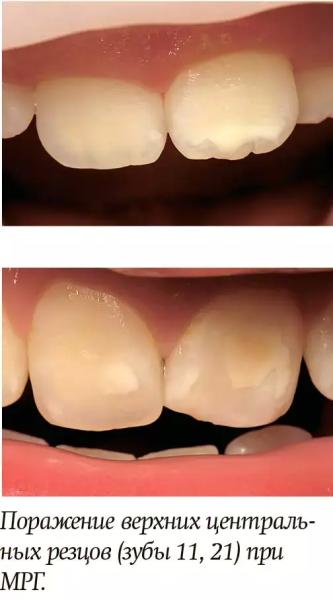

Жанна БуракМРГ представляет собой нарушения формирования твердых тканей постоянных зубов (от 1 до 4 первых моляров и/или резцов), которые наблюдаются при их прорезывании и проявляются в виде участков непрозрачной эмали, ее помутнения с четко определяемой границей между пораженной и неизменной тканью (опаковостью). Эмаль первых моляров приобретает желтоватый цвет с порами — «сырные» зубы. На резцах пятна имеют белую или желтую окраску. Зубы чувствительны к механическим и температурным раздражителям.

Выделяют 2 формы МРГ: легкую и тяжелую. При первой форме быстрой утраты эмали пораженных участков не происходит, эстетические проблемы, связанные с изменением цвета резцов, незначительны, чувствительность индуцированная (т. е. наблюдается к внешним раздражителям, например, к воздуху/воде, но не к чистке зубов). При тяжелой форме МРГ ограниченные очаги опаковости сопровождаются утратой эмали и быстрым присоединением кариеса. Изменение цвета резцов приводит к выраженным эстетическим нарушениям, которые могут иметь социально-психологические последствия; гиперчувствительность зубов спонтанная и стойкая, влияющая на функции (например, чистку зубов, жевание).